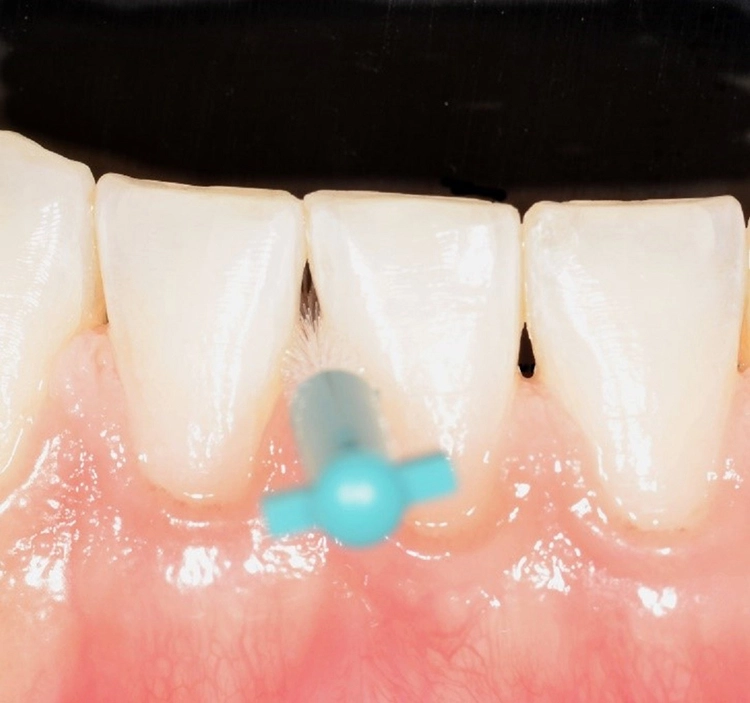

Dabei umfassen die ISO-Gruppengrößen 1 bis 3 jeweils zwei PHD-Werte, die Größen 4 bis 5 drei und die Größen 6 bis 7 fünf PHD-Werte. Alle Bürsten mit einem PHD von > 2,9 erhalten die ISO-Größe 8. Obwohl die neue Norm ein großer Fortschritt ist, führen die heterogenen ISO-Gruppengrößen vor allem bei größeren Interdentalraumbürsten zu ungenügender Differenzierung. Nicht alle Bürsten der gleichen ISO-Gruppengröße können denselben Interdentalraum passieren (Abb. 3). Entscheidend ist daher die Orientierung am einzelnen PHD-Wert und nicht an der ISO-Gruppengröße [28].